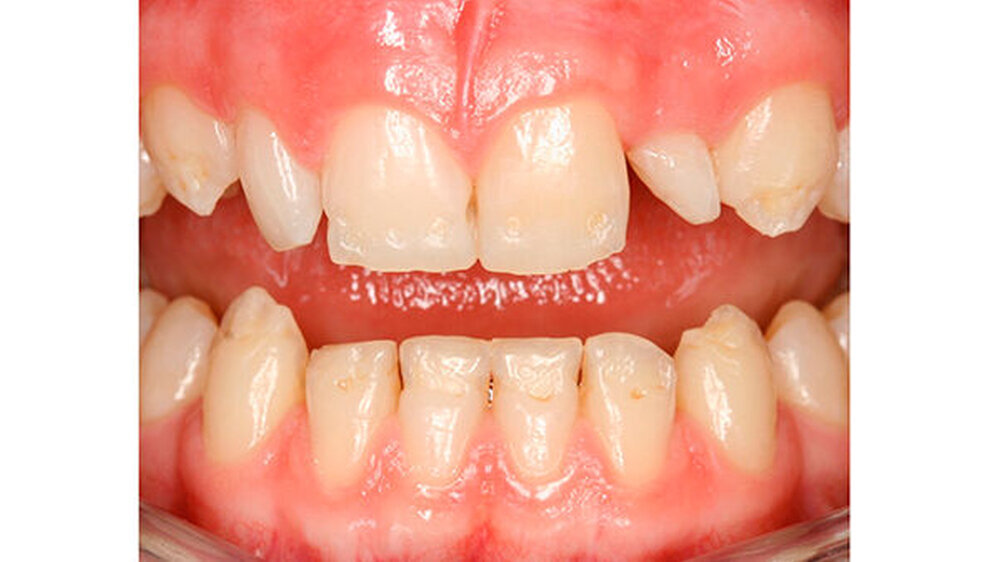

Das klinische Bild der MIH reicht von einem bis zu vier betroffenen Molaren, nur selten sind alle Zähne in ähnlicher Ausprägung geschädigt [Weerheijm et al., 2001]. Die bleibenden Frontzähne können ebenfalls betroffen sein, diese weisen allerdings in der Regel keinen Schmelzeinbruch auf und sind selten bis gar nicht überempfindlich [Weerheijm et al., 2001] (Abbildung 2).